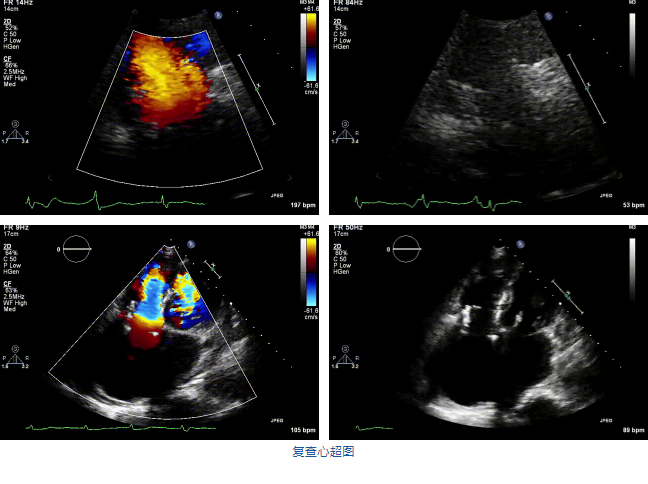

2021年12月7日,復旦大學附屬中山醫(yī)院葛均波院士團隊完成的首批兩例LuX-Valve Plus經(jīng)血管三尖瓣置換患者順利出院,從患者入院至出院僅歷時一周時間,出院時患者狀態(tài)恢復良好,復查心超三尖瓣無反流。

兩例患者是都是外科手術高危的極重度三尖瓣反流的老年女性,反復下肢水腫、腹脹、納差,活動耐力減退。一例患者風濕性心臟病,二尖瓣生物瓣置換術后,房顫,心超顯示三尖瓣極重度反流(最大反流寬度15mm);另一例患者房顫,心超示三尖瓣極重度反流(最大反流寬度23mm)。

結合術前CT評估結果,葛均波院士團隊最終決定選用LuX-Valve Plus 50mm和55mm兩種型號的瓣膜,并于2021年11月30日順利完成LuX-Valve Plus經(jīng)血管三尖瓣置換術,手術室即刻拔除氣管插管,術后第二天轉(zhuǎn)出心內(nèi)科監(jiān)護室,下床活動。術后患者三尖瓣反流癥狀得到顯著改善,復查心超結果顯示人工三尖瓣瓣膜支架固定穩(wěn)定,瓣葉關閉形態(tài)未見異常,未見明顯反流。